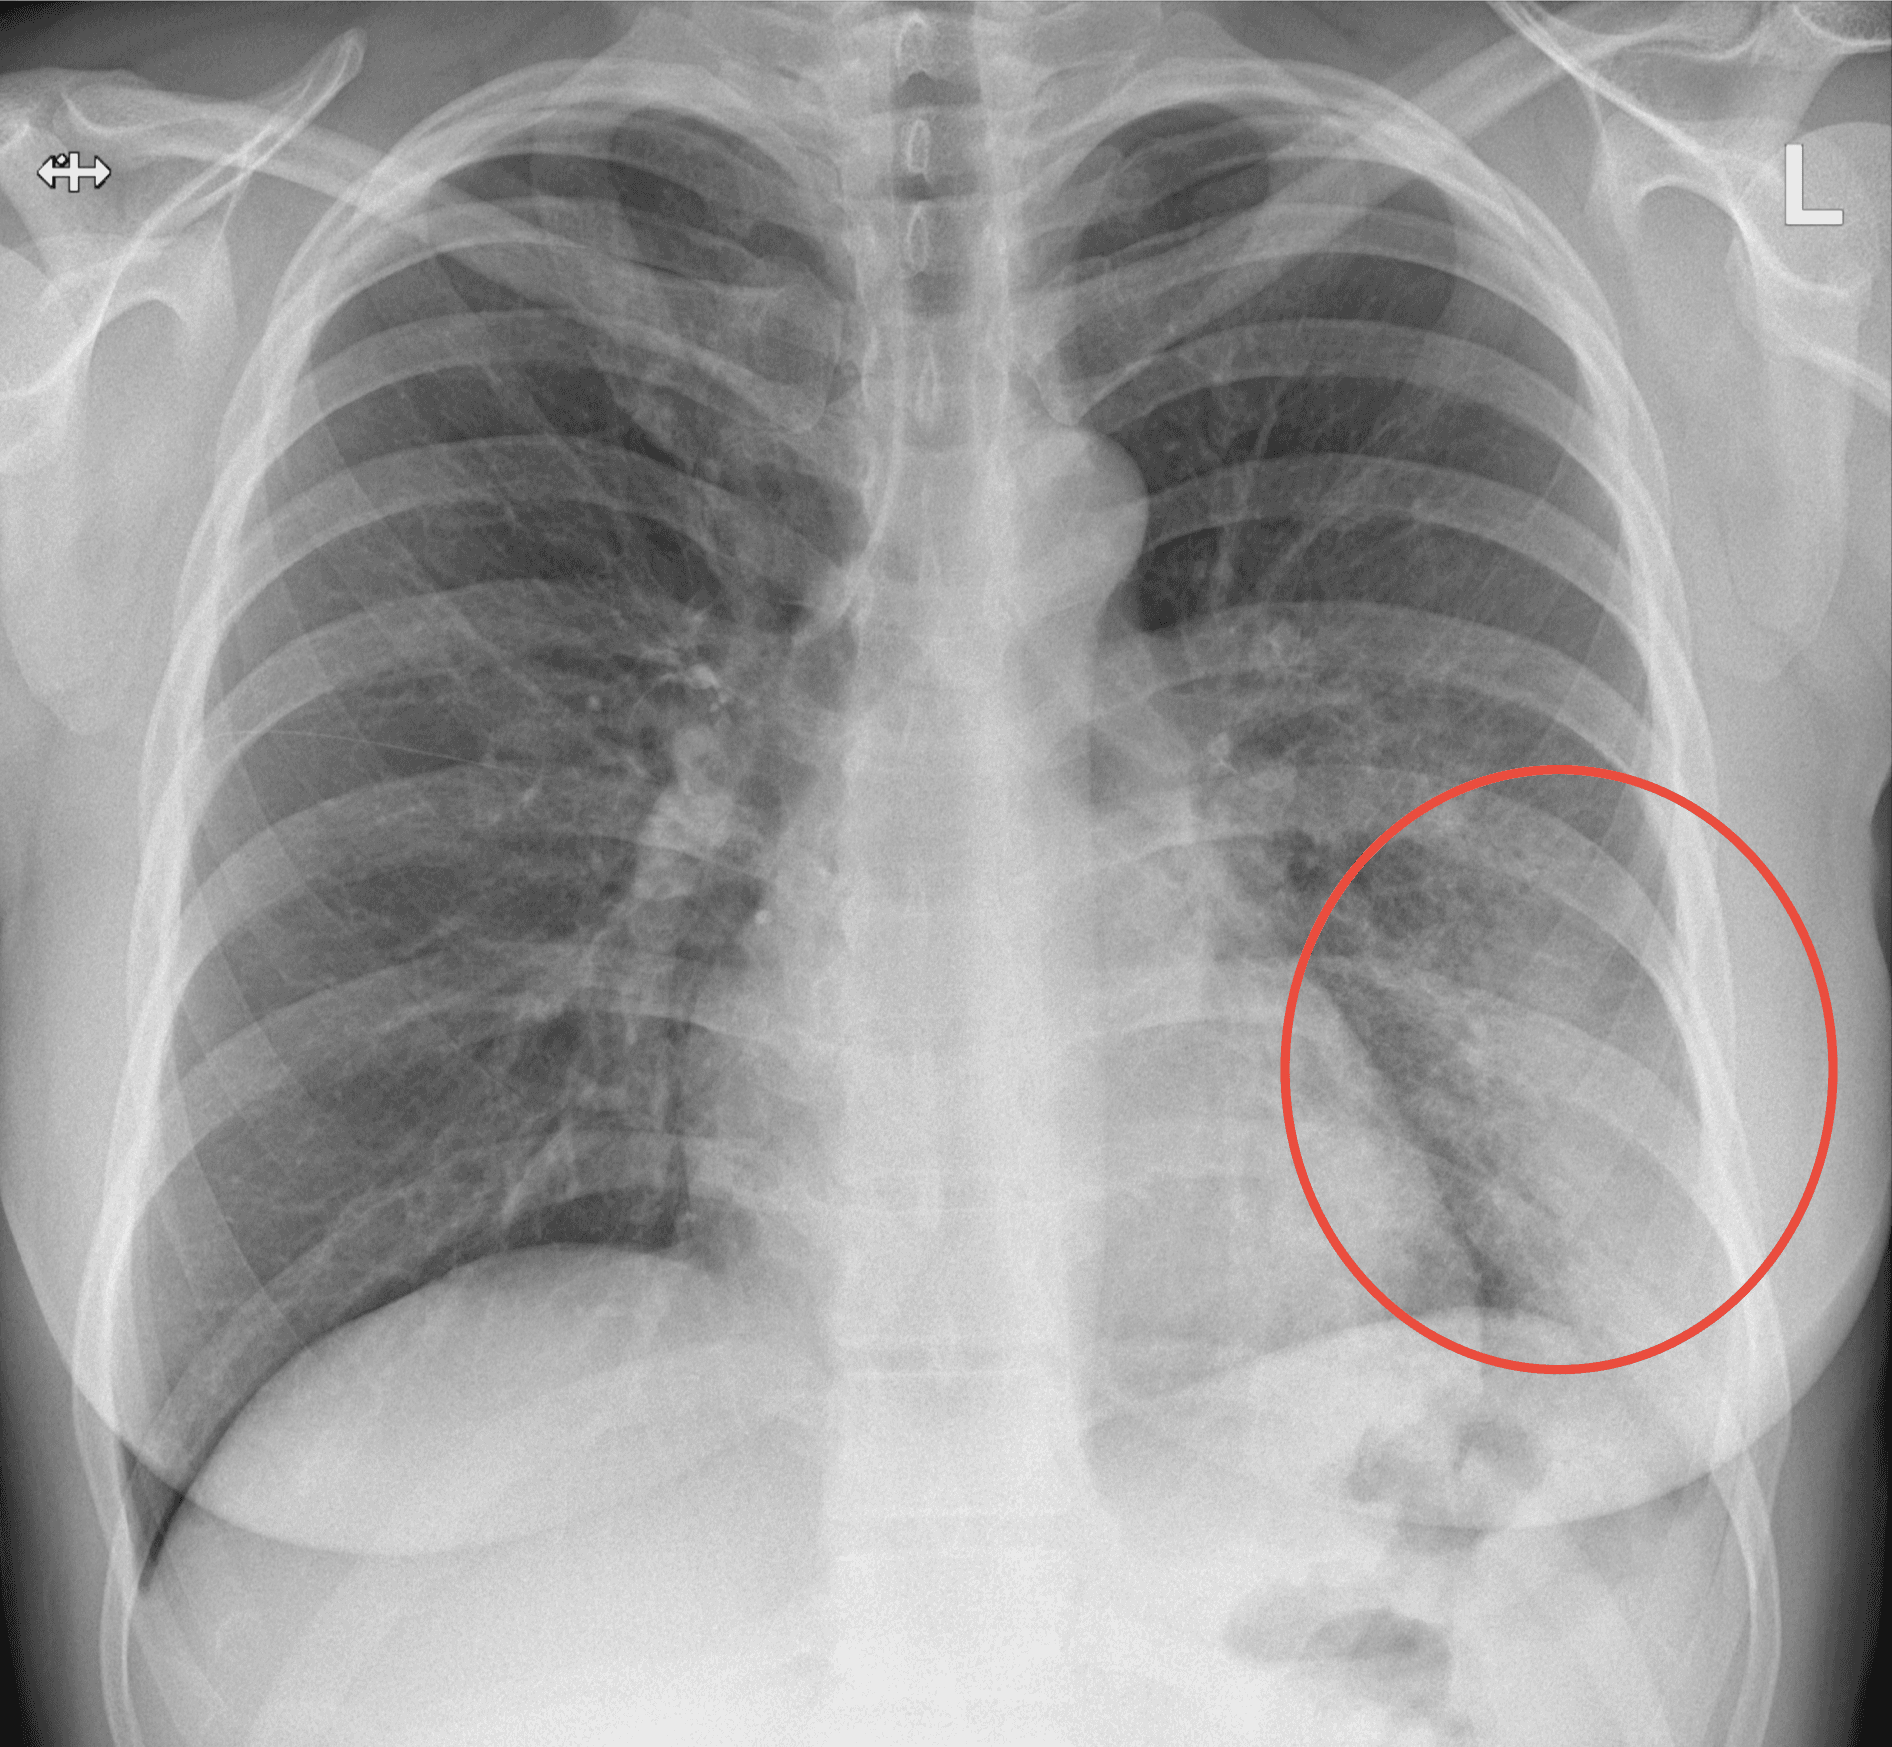

98% certainty

Medusa detected Emphysema in the lungs